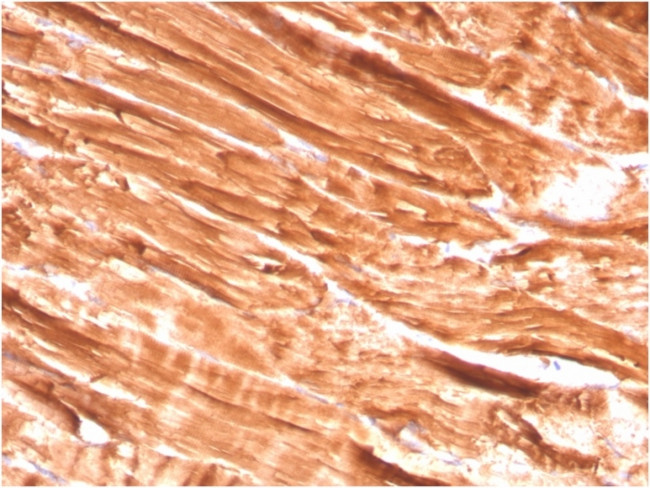

Dystrophin (DMD) Antibody in Immunohistochemistry (Paraffin) (IHC (P))

图: 1 / 4

Dystrophin (DMD) Antibody (1756-MSM2-P1ABX) in IHC (P)

Immunohistochemistry (Paraffin) analysis performed in formalin fixed, paraffin-embedded human skeletal muscle using Dystrophin (DMD) Monoclonal Antibody (Product # 1756-MSM2-P1ABX). {{ $ctrl.currentElement.advancedVerification.fullName }} 验证信息 View more